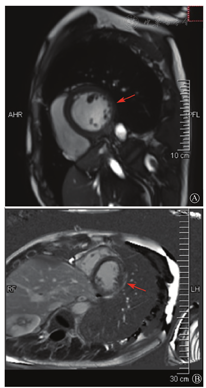

患者入院后无特殊不适,心率70次/min,血压110/60 mmHg,心功能Ⅱ级。查血常规:血红蛋白139 g/L,白细胞7.39×109/L,血小板221×109/L。尿常规、便常规+潜血均正常。生化:丙氨酸氨基转移酶38 U/L,白蛋白47 g/L,钾3.9 mmol/L,肌酐(酶法)65 μmol/L,总胆固醇3.52 mmol/L,低密度脂蛋白胆固醇2.08 mmol/L。CK:1 256→487 U/L,CK-MB 9.7→3.8 μg/L,cTnI 85.90→68.50 pg/ml。N末端B型利钠肽原70 pg/ml。CK同工酶电泳:肌酸激酶MM质量100.0%(此时CK-MB已正常)。血沉1 mm/第1小时,高敏C反应蛋白1.61 mg/L;补体:C3 0.876 g/L,C4 0.174 g/L。免疫球蛋白:IgG 9.52 g/L,IgA 1.73 g/L,IgM 0.62 g/L。血清蛋白电泳未见M蛋白。糖化血红蛋白5.1%。乳酸(运动前)1.1 mmol/L,乳酸(运动中)6.6 mmol/L,乳酸(运动后)7.8 mmol/L。肌炎抗体谱:抗PM-SCL75(+),余均(-)。心电图:aVL、V5、V6导联T波倒置(图2)。冠状动脉CT未见明显异常。超声心动图:左室舒张末内径55 mm,左室收缩功能减低,心尖部、左室壁普遍运动减低,以左室下后壁为著,左室下后壁肌小梁明显增多可见隐窝,疏松层与致密层之比为1.7;左室射血分数(双平面)45%;右冠状动脉开口6.5 mm,开口处未见明确瘤样扩张(图3)。

A:胸骨旁长轴平面,左室舒张末内径略增大,室壁无明显增厚;B:胸骨旁左室短轴切面心尖水平,可见心肌肌小梁增多,其内可见隐窝(箭头所示)